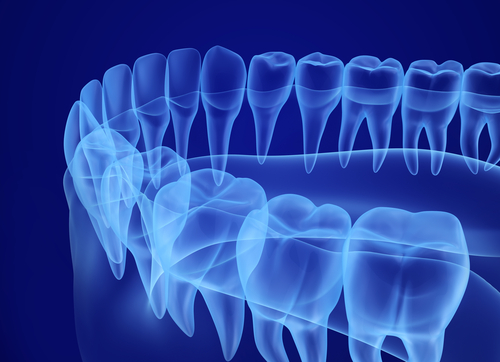

With this technology, you can visualize detailed anatomical structures critical for diagnosis and treatment planning. This improves our ability to explain your case, answer questions, and plan procedures such as implant placement, impacted tooth exposure, and TMJ evaluations with superior precision.